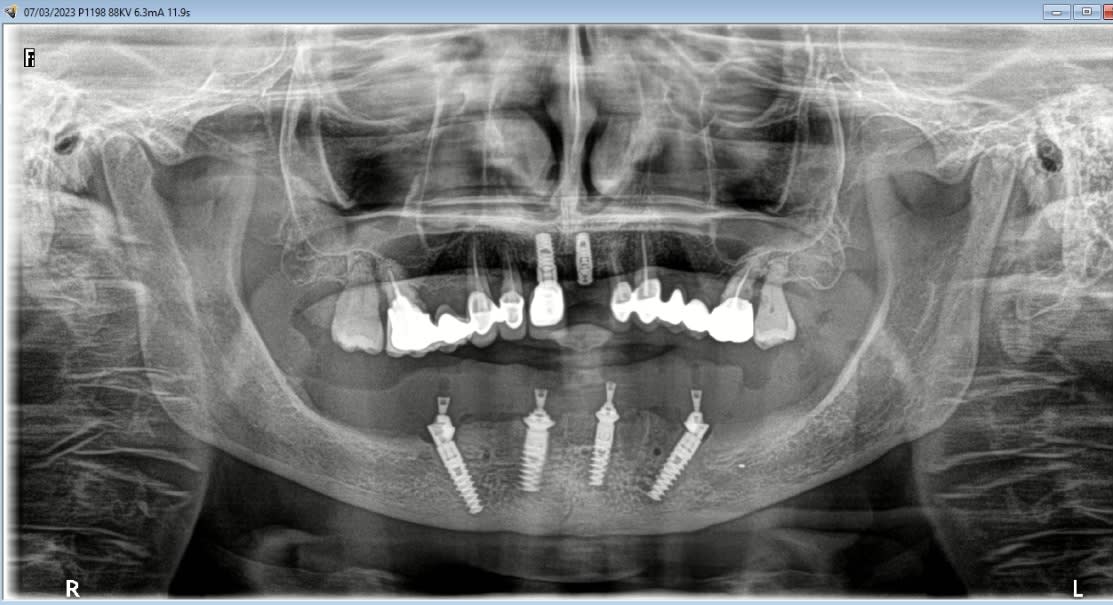

Planif BSP, export meshmixer et réalisation du guide en fusion laser ( Fridentech ).

Impression modele osseux et simulation de la chir.

Tres important pour la mise en charge instantanée : la precision : bien indexer les implants sur le guide en cas de piliers angulés.